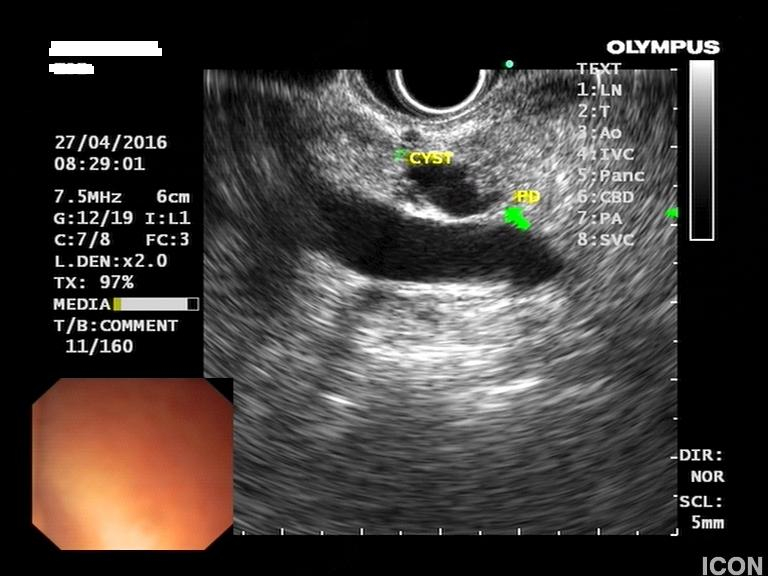

Γυναίκα 58 ετών, υποβλήθηκε προληπτικά σε υπέρηχο άνω κοιλίας όπου διαπιστώθηκε μια κύστη στην κεφαλή του παγκρέατος. Το εύρημα επιβεβαιώθηκε σε μαγνητική τομογραφία (MRI/MRCP) που δεν έδειξε άλλα παθολογικά ευρήματα στο πάγκρεας. Ο ενδοσκοπικός υπέρηχος έδειξε μια δίχωρη κύστη, διαστάσεων 6,5Χ12,5 χιλ, στην παγκρεατική κεφαλή.

Η κύστη είχε επικοινωνία με κλάδο του παγκρεατικού πόρου, ενώ ο μείζων παγκρεατικός πόρος ήταν φυσιολογικής διαμέτρου σε όλη την πορεία του. Επίσης, διαπιστώθηκε δεύτερη κύστη διαμέτρου 2,5χιλ στο σώμα του παγκρέατος που δεν είχε απεικονιστεί στην MRI.

Έγινε βιοψία με λεπτή βελόνα 22g (FNA) και αναρροφήθηκε πλήρως η κύστη της κεφαλής. Οι βιοχημικοί δείκτες του υγρού της κύστης ήταν: CEA 467, αμυλάση 1550.

Τα ευρήματα ήταν συμβατά με ένα ενδοπορικό θηλώδες βλεννώδες νεόπλασμα των κλάδων του πόρου (branch-duct IPMN).

Κύστη κεφαλής παγκρέατος

Επικοινωνία κύστης με παγκρεατικό πόρο